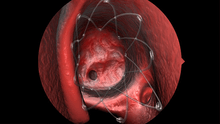

Sinus stent

Propel mometasone furoate implant is a sinus implant used to treat inflammation associated with sinusitis. It is used as a stent and inserted into the sinus cavity during sinus surgery[7] after an ethmoidectomy procedure, which removes bony partitions within the ethmoid sinus.[8] It delivers steroids over a 30-day period to treat chronic sinusitis.[9] The implant dissolves over four to six weeks and does not require removal from the sinus cavity, as well as reduces the need for additional surgical procedures and steroid pills, which can have detrimental side effects.[10] The device was approved by the United States Food and Drug Administration on August 11, 2011.[11]

A randomized, double-blind pilot study of sinus stents using 43 patients during an eight-week trial period showed no adverse effects.[12] The intra-patient control design compared a drug-eluting implant to a non-steroid eluting implant. It also showed adhesion rates of 5.3% for those using Propel in comparison to 21.1% for those who received a non-steroid eluting implant.[13][14] The trial showed less than 10% of stent material present after 30 days with the remaining completely absorbed by the end of the eight week trial.[12][13]